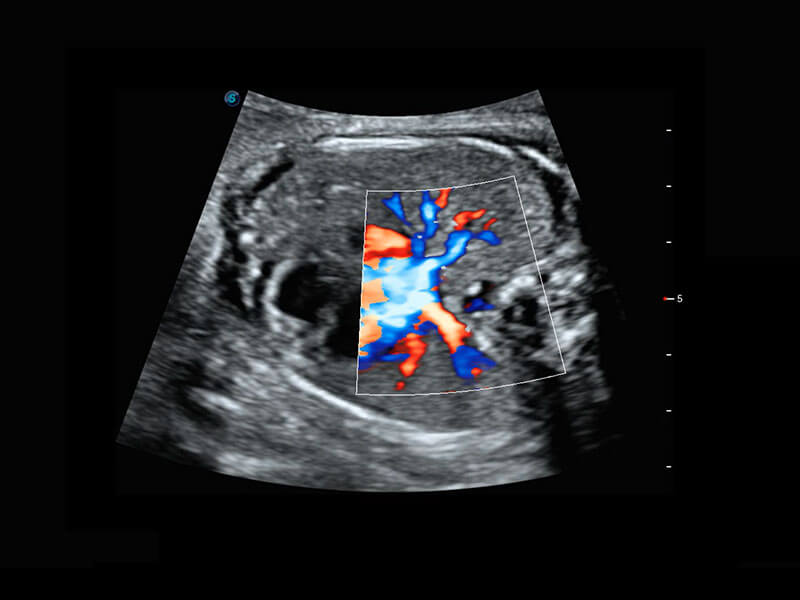

胎儿体循环